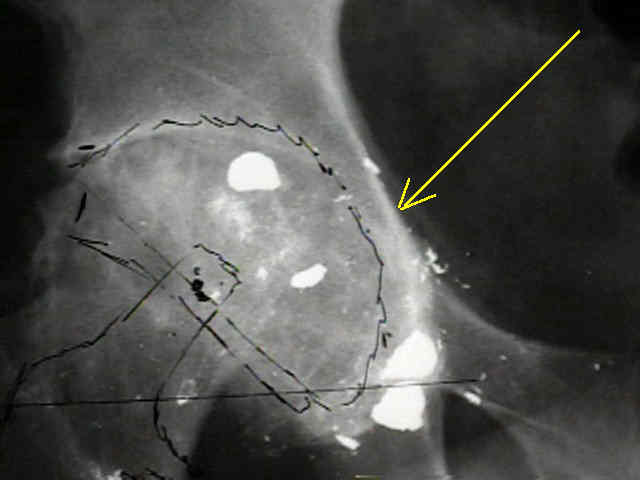

Case Example

- 35-year-old male w/ near anklyosed hip following a GSW to the hip;

- preoperative films appeared to indicate that little or no medialization was necessary;

- postoperative films, however, indicate that the cup was lateralized (hence, reaming was inadequate);

- in retrospect, the radiographs which are rotated externally (like an iliac oblique) tend to falsely minimize the necessary amount of medialization where as X-rays which are rotated internally (like an obturator oblique), tend to over-estimate the necessary amount of medialization